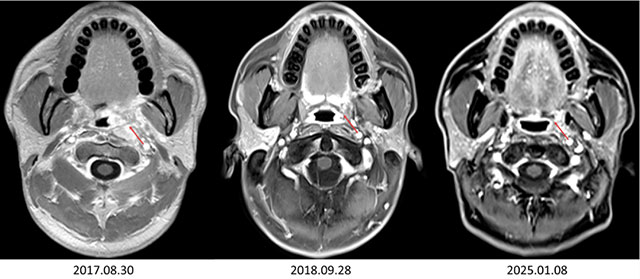

经过系统治疗后,李大哥的左耳胀闷、听力下降等症状逐渐缓解,肿瘤也得到了有效控制。治疗结束后,李大哥严格遵循曾瑞的嘱咐,定期复查、规律作息、合理饮食,坚持中医调理。

如今,8年多时间过去,李大哥已完全回归正常生活,不仅能照顾家人,还能正常工作。

近日,他再次来到医院复查,检查结果显示病情无复发转移,达到了“临床治愈”的标准。